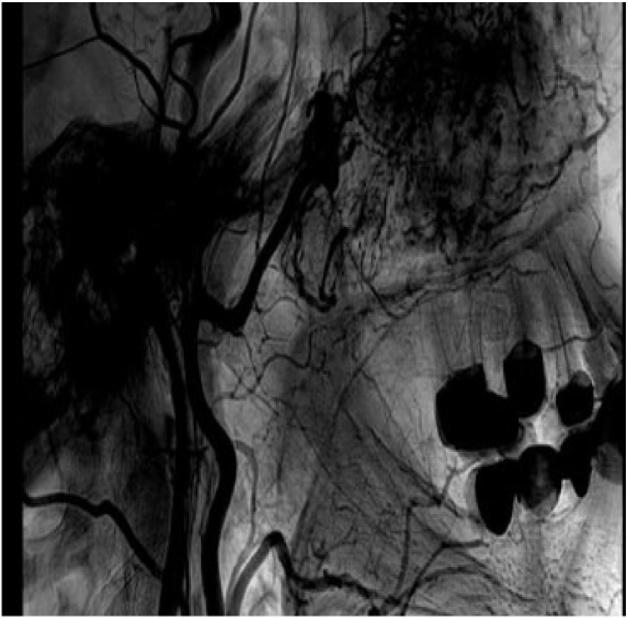

We present a case of a 37 year-old female diagnosed with a paranasal large size hemangioma treated with functional endoscopic sinus surgery (FESS).

The case had a rare anatomical location of the hemangioma, along with a minimally invasive approach for a large size hemangioma. Owing to that fact, it might be challenging to differentiate between paranasal sinus hemangiomas and other benign or malignant pathologies.

While paranasal sinus hemangiomas occur rarely, they have arisen from the paranasal sinus mucosa. They have an average size of 1 cm, and have been reported to be as large as 8 cm, similarly to this case. When larger in size, hemangioma resections are usually approached through open surgery, whereas, in this case, the hemangioma was resected completely by FESS.